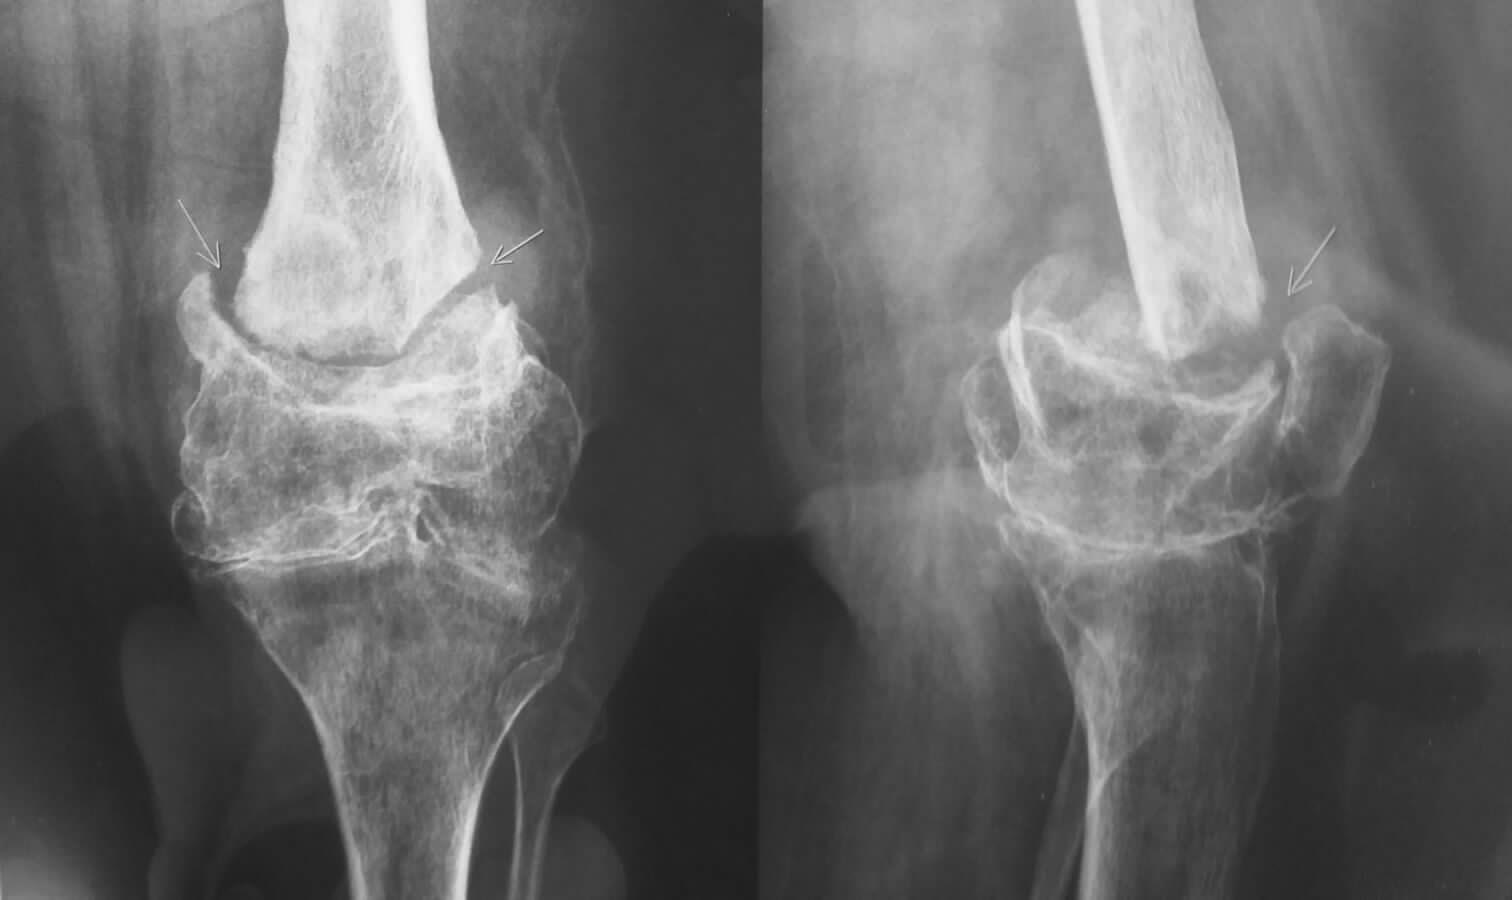

Женшина 69 лет В прошлом году произведена корригирующая остеотомия в н/3 бедра по поводу вальгусной деформции бедро фиксировано в аппарате Иллизарова.

В связи с инфицированием аппарат демонтирован. В настоящее время конечность не опороспособна, движений в коленном суставе нет.Планируем закрыто синтезировать ретроградно БИОС реконструктивным стержнем СНМ.

По-моему, это как раз тот самый крайний вариант. Сложнейший ложный сустав, никакой коленный. И это ведь мы только маленький кусочек ноги видим. А что выше и ниже? Спицевой остеомиелит? Ведь сняли же аппарат из-за инфекции. Что за инфекция? И гвоздь то страшно в такую ногу. Не то что протез. Было бы здорово, если бы кто-то из рекомендующих протезирование выложил рентгенограммы хоть отдаленно напоминающего данный случай примера из своей практики.

Мы успешно делали антеградный интрамедуллярный остеосинтез при переломах и несращениях этой локализации много раз. Но тут действительно чистый остеосинтез не решение, поскольку сустав разрушен. И так, абстрактно, действительно варианты - это артроодез или замена сустава.

Но в конкретных обстоятельствах - инфекция, пожилой возраст - предпочтительнее выглядит артродез с фиксацией длинным стержнем, еще и с антибактериальным покрытием. Такую операцию можно сделать во многих клиниках России.

А какова цель остеосинтеза при разрушенном коленном суставе в котором уже нет движений? Добьетесь сращения - будет болеть коленка. И что дальше? Через 2 года убрать гвоздь и поставить протез?

Женщина уже устала лечиться, нога в месте ложного сустава нестабильна. Один год передвигается на костылях. В аппарате Илизарова находилась полгода, в настоящее время от чрезкожного остеосинтеза категорически отказалась.

Вечер добрый! На мой взгляд если пациентке не нужна функция в коленном суставе, то артродез любым способом,предпочтительно длинным гводем с рассверливанием и антибактериальным покрытием цементом с антибиотиком(не исключена инфекция). Если бороться за функцию,то в данном случае видится онкологический протез. Опять же после решения вопроса с возможной инфекцией зоны псевдоартроза и коленного сустава. С уважением, Руслан.